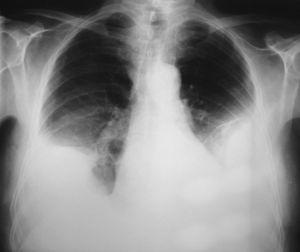

Los estudios de laboratorio fueron normales, incluidos número de plaquetas, valores de la coagulación, dímero D, hormonas tiroideas, antígeno carcinoembrionario o marcadores de colagenosis. La cifra de hematíes plasmáticos era de 3.370.000 /μl, la hemoglobina de 10,5 g/dl y el hematocrito del 30%. La exploración rectal y el sedimento de orina fueron normales. La prueba de la tuberculina fue negativa. El Doppler de las extremidades inferiores y la gammagrafía pulmonar de ventilación/perfusión descartaron una enfermedad tromboembólica venosa. La tomografía axial computarizada toracoabdominal con contraste intravenoso confirmó la presencia de un derrame pleural bilateral, con un engrosamiento homogéneo de ambas pleuras y sin lesiones parenquimatosas, mediastínicas, infradiafragmáticas o imágenes indicativas de embolia pulmonar (fig. 2).

Fig. 2. Tomografía axial computarizada de tórax con contraste intravenoso. Derrame pleural bilateral con engrosamiento pleural.